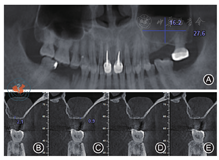

。锥形束CT(cone beam computed tomography,CBCT)示:25、26牙槽嵴高度0.9~ 2.1 mm,左侧上颌窦可见弥漫性大小为27.6 mm × 16.2 mm低密度影(图1)。诊断:上颌牙列缺损。治疗方案:行牙周基础治疗;保留上颌窦囊肿的前提下行上颌窦外提升骨增量术,待25、26区牙槽嵴高度足够时再行Ⅰ期牙种植手术。

注:图1A为初诊时的全颌曲面断层影像;图1B~ 1C为25唇颊侧切面;图1D~ 1E为26唇颊侧切面